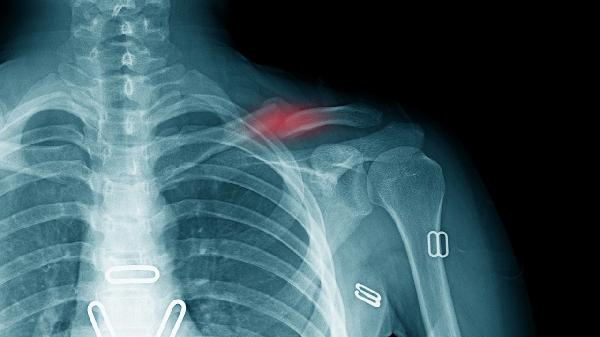

肩膀鎖骨骨折吃什么好得快

肩膀鎖骨骨折后可通過(guò)高蛋白飲食、鈣質(zhì)補(bǔ)充、維生素D攝入、抗氧化食物及水分補(bǔ)充促進(jìn)愈合。鎖骨骨折的恢復(fù)主要與營(yíng)養(yǎng)支持、局部制動(dòng)、康復(fù)鍛煉等因素相關(guān)。